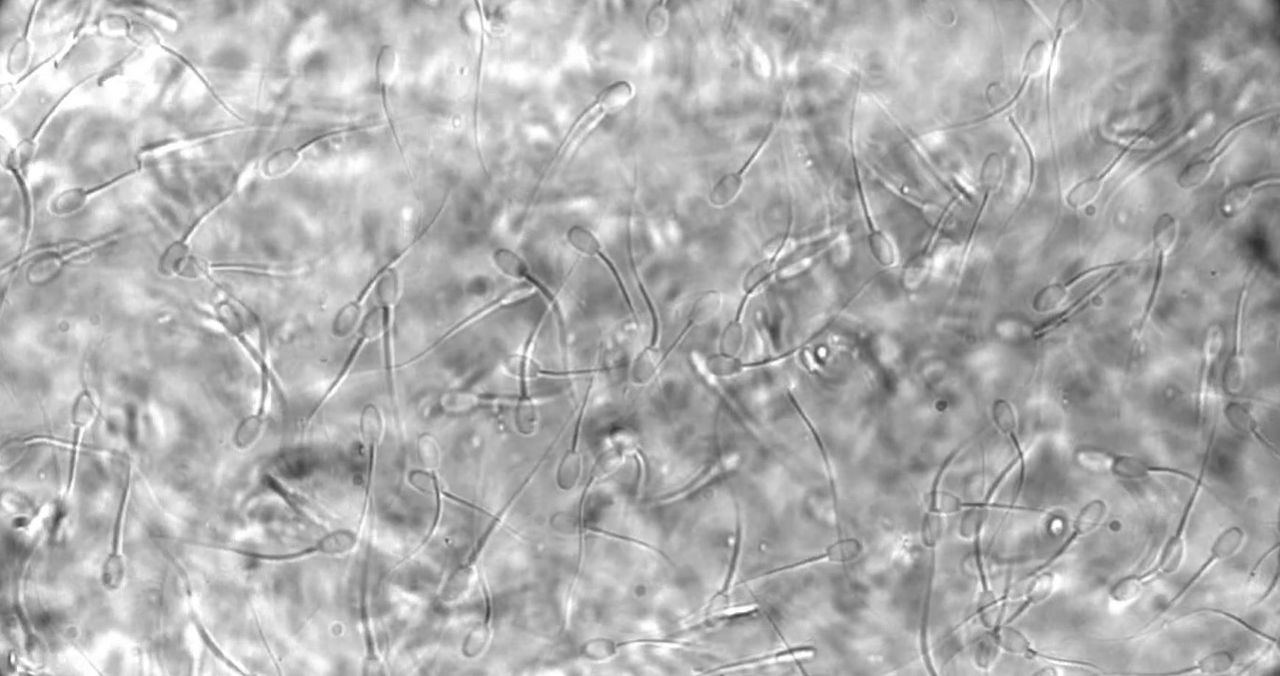

Forskare testar nytt hormonfritt preventivmedel för kvinnor Hindrar spermierna att nå ägget Forskare testar nytt hormonfritt preventivmedel för kvinnor Forskare vid bland annat KTH, KI och Karolinska Universitetssjukhuset har kommit långt med testerna av ett nytt hormonfritt preventivmedel för kvinnor. Det handlar om en vaginal gel som stärker den naturliga barriär som finns i livmoderhalsen och på så vis hindrar spermierna att nå fram till ägget. Tester på får visar att gelen fungerar.Thomas Crouzier, forskare vid avdelning Glykovetenskap på KTH och ansvarig för arbetet säger följande:"Slembarriären är vanligtvis sluten och inte penetrerbar för spermier, men öppnar sig vid tidpunkten för ägglossning för att möjliggöra befruktning. Vi visar att med hjälp av en vaginal gel bestående av bland annat en polymer kan vi modifiera barriärens fysiska egenskaper och göra den ogenomtränglig för spermier. Vaginala geler som denna kan appliceras på några sekunder. Vi tänker oss att en sådan här produkt ska kunna användas från sekunder till någon timme innan sexuell umgänge. Effekten skulle då kunna bestå i timmar, men avta allt eftersom slembarriären byts ut på naturlig väg, och därmed också gelen."Läs mer på länken nedan. mynewsdesk.com Vetenskap, Forskning, hormonfritt, preventivmedel, kvinnor, tester,